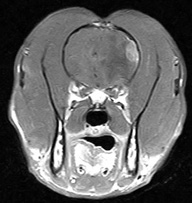

延髄髄内腫瘍